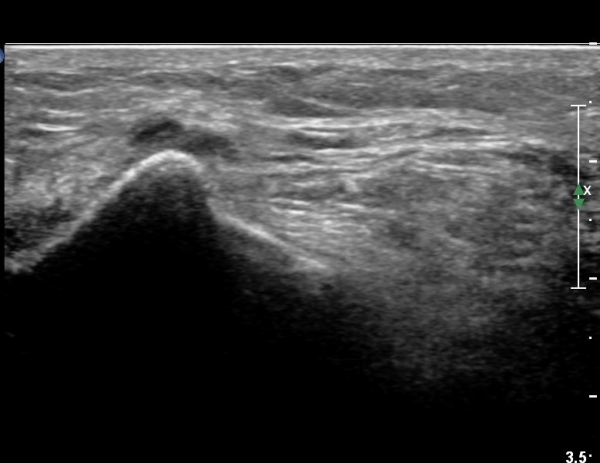

¹«¸­ ¿À±Ý ºÎÀ§ Ⱦ´Ü¸é°Ë»ç¿¡¼­ °æ°ñµ¿¸Æ Ç¥Ãþ¿¡ ºñ°ñ½Å°æ°ú °æ°ñ½Å°æÀÌ ºÐ¸®µÇ¾î °üÂûµÈ´Ù(»çÁø 1).

ŽÃËÀÚ¸¦ ¸»´ÜÀ¸·Î À̵¿ÇÏ´Ï À̵ιڱ٠³»Ãø¿¡¼­ ºñ°ñ½Å°æ¿Í °üÂûµÈ´Ù(»çÁø 2).